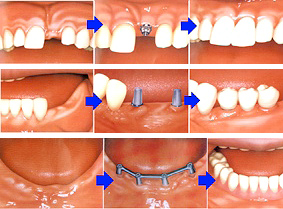

御存知の通り「インプラント治療」とはチタン合金のネジを顎骨に埋めて、その上に「歯」のようなものを載せ、その「人工の歯」を使って咀嚼を助ける治療のことです。「歯が1本抜けたらインプラントを1本埋める」のように1対1が理想です。インプラントが使われるまでは「ブリッジ」という治療法が一般的でした。なぜ「一般的」なのかと言えば、選択肢が取り外し式の「入れ歯」か、固定式の「ブリッジ」しかなかったからです。「入れ歯」は患者さんに嫌われました。下顎の入れ歯の場合は食事中に外れやすく、入れ歯の一部が舌の先が当たって邪魔なので、入れ歯を作ってもほとんど使われません。しかし、過大な咬合力が長期間小臼歯に懸かると徐々に歯を壊していきます。神経の死んでいる歯の場合は必ず折れます。小臼歯まで無くなればさすがに食事は困難を極めます。お友達と食事に行けば、いくら急いで食べても食べ終わるのは最後です。咀嚼せずに飲み込むので常に胃腸の具合が悪く、消化薬を常用しています。唯一の救いは、お友達と一緒に旅行に行ったときに入れ歯を外すところを見られずに済むことぐらいでしょうか。正面からの見た目だけは維持されますから、なんとか我慢できるのでしょう。

御存知の通り「インプラント治療」とはチタン合金のネジを顎骨に埋めて、その上に「歯」のようなものを載せ、その「人工の歯」を使って咀嚼を助ける治療のことです。できれば「1本歯が抜けたら1本インプラントを埋める」ように1対1の方法が理想です。インプラントが出るまではブリッジという治療法が一般的でした。選択肢が取り外し式の「入れ歯」か、固定式のブリッジしかなかったからです。しかし、一番後ろの歯がなくなると入れ歯しかありませんでした。特に下顎の入れ歯の場合は食事中に外れやすく、入れ歯の一部が舌の先が当たって邪魔なので、入れ歯を使わなくても食事できる場合はほとんど使われません。大臼歯2本無くても充分に食事はできます。しかし、過大な咬合力が長期間小臼歯に懸かると徐々に歯を壊していきます。生きている歯は折れることはありませんが、神経の死んでいる歯の場合は必ず折れます。小臼歯も無くなればさすがに食事は難しくなります。お友達と食事に行けば、急いで食べても食べ終わるのは最後です。そして常に胃腸の具合が悪く、消化薬を常用しています。唯一の救いは、お友達と一緒に旅行に行ったときに入れ歯を外すところを見られずに済むことぐらいでしょうか。正面からの見た目だけは維持されますから、なんとか我慢できるのでしょう。斜め45度じゃバレます。

インプラントがこれほど流行する背景には高い成功率があります。普通のケースは5年間95%成功しますし、患者さんの満足度も高いと思います。これほど高い成功率、満足度は普通の歯科治療でもあまりありません。入れ歯に成功失敗があるかどうかはわかりませんが、たとえ「成功」しても患者さんの満足度は非常に低いでしょう。しかし、近頃はどんどん患者さんの要求が高くなり「審美的な成功」を求めるケースも多くなりました。前歯部のインプラントを審美的に仕上げるのは本当に高度な技術です。